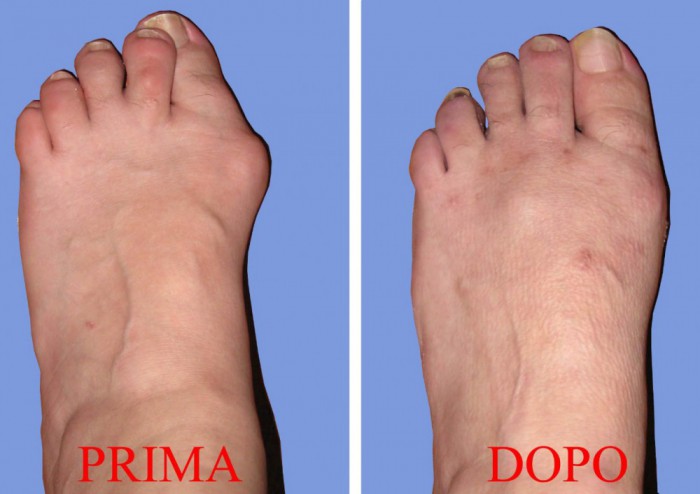

L’Alluce valgo è una deformità del piede che consiste in un’inclinazione dell’alluce (il primo dito del piede) verso le altre dita con la contemporanea deviazione del primo osso metatarsale ( che si articola con l’alluce) verso l’interno. Si crea quindi una deformità a zig zag che accorcia ed allarga il piede e determina la tipica sporgenza ossea chiamata esostosi o più comunemente “cipolla” la quale provoca una serie di non trascurabili conseguenze come arrossamento, dolore, infiammazioni (borsiti) e talvolta ulcerazioni, e rende sempre più difficile camminare normalmente ed indossare calzature di qualsiasi genere.

In genere, all’inizio si tratta di una semplice (anche se non piacevole) questione estetica ma successivamente subentra l'insufficienza funzionale dell'alluce

La progressiva inclinazione laterale fa si che durante la deambulazione la spinta dell'alluce diventi poco efficace trasferendo il carico sulla parte laterale del piede e quindi comportando un sovraccarico sui metatarsi centrali.

Inoltre, l’alluce inclinandosi lateralmente determina una spinta sulle dita esterne che risultano quindi progressivamente deviate verso l'esterno e costrette a trovare un loro spazio sollevandosi ( iperestensione) con lussazione progressiva dell’articolazione metatarso-falangea. Tale deformità delle dita denominata o “a martello” o “ad artiglio” aggravano maggiormente il sovraccarico delle teste metatarsali

A lungo andare la deviazione e l’insufficienza funzionale dell’alluce può portare a callosità e ulcerazioni nella parte anteriore del piede in corrispondenza delle teste metatarsali, tali da provocare un dolore cosi intenso da impedire l’uso di calzature o, nei casi più gravi, l’appoggio del piede. Inoltre, la deformazione progressiva del piede, oltre a generare dolori, determina un appoggio alterato e un’alterazione del passo che può avere ripercussioni serie su altre strutture, quali ginocchia, anche e colonna vertebrale.

Con un’unica operazione chirurgica senza tagli e senza impiego di mezzi di sintesi ( viti, chiodi, cambre o fili di ferro) si può risolvere per sempre tutte le problematiche variamente connesse alla presenza dell’alluce valgo, ripristinando la corretta funzionalità della deambulazione permettendo al paziente di tornare a indossare calzature normali.

Nessuna cicatrice o punti di sutura sulla pelle. Dopo l’operazione viene confezionato solo un particolare bendaggio che mantiene una valida e giusta correzione.